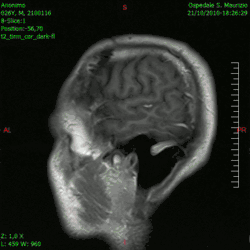

En las imágenes de TC y RM se muestra como una lesión heterogénea, de contorno irregular, que capta contraste en anillo y con un área central necrótica.

Diagnóstico por imagen y glioblastoma

La TC muestra una lesión de morfología irregular, predominantemente hipodensa y fuertemente dishomogénea, debido a la presencia de grandes áreas necróticas de más clara hipodensidad y de áreas sólidas hiperdensas. Estas últimas son la expresión de un rápido crecimiento y por lo tanto de una elevada malignidad. Son frecuentes las zonas hemorrágicas, que van desde pequeños focos a grandes áreas hemáticas que pueden cubrir toda la lesión. Es característica la morfología en "mariposa" si el tumor se asienta en ambos hemisferios a través del cuerpo calloso.

Tras la aplicación de contraste aparecen gruesos anillos alrededor de las áreas necróticas. En la RM, la parte sólida aparece hipointensa en T1 e hiperintensa en T2 con zonas de señal más elevada en las partes de mayor celularidad. Las áreas necróticas, hiperintensas en T2, pueden presentarse hipo-, iso- o hiperintensas en T1 en función del contenido proteico o de productos de la degradación de la hemoglobina. El realce tras el contraste suele ser intenso e irregular en la periferia del tumor e identifica sobre todo la componente celular "proliferativa" de la neoplasia. Son comunes las áreas puntiformes y serpiginosas de ausencia de señal de flujo, asociadas a la presencia de una neovascularización rica. Estos vasos de neoformación patológica carecen de barrera hematoencefálica, lo que explica tanto la abundante impregnación como el edema vasogénico perilesional (véase la sección anterior), debido al paso de líquido al medio extracelular.[72][73]